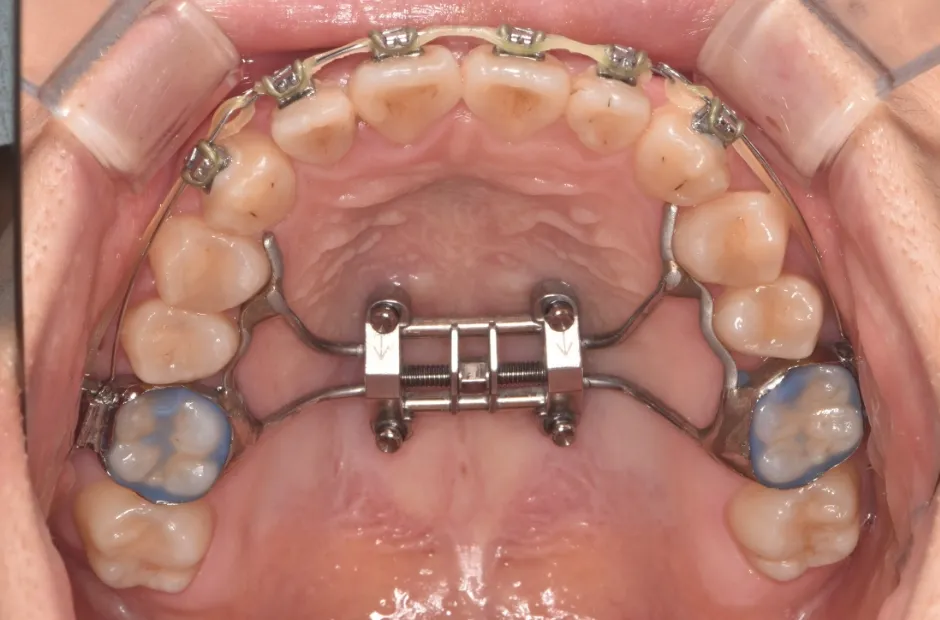

| 診断名・主訴 | ゆがみ(左右非対称) |

|---|---|

| 年齢・性別 | 20歳・女性 |

| 治療期間・回数 | 2年半 30回 |

| 治療に用いた主な装置 | 急速拡大 アンカー |

| 抜歯部位 | 左右上5番 |

| 治療費 | 70万円(税抜) |

| リスク・副作用 | 装置による違和感・疼痛・歯肉退縮・歯根吸収・虫歯のリスクなど |